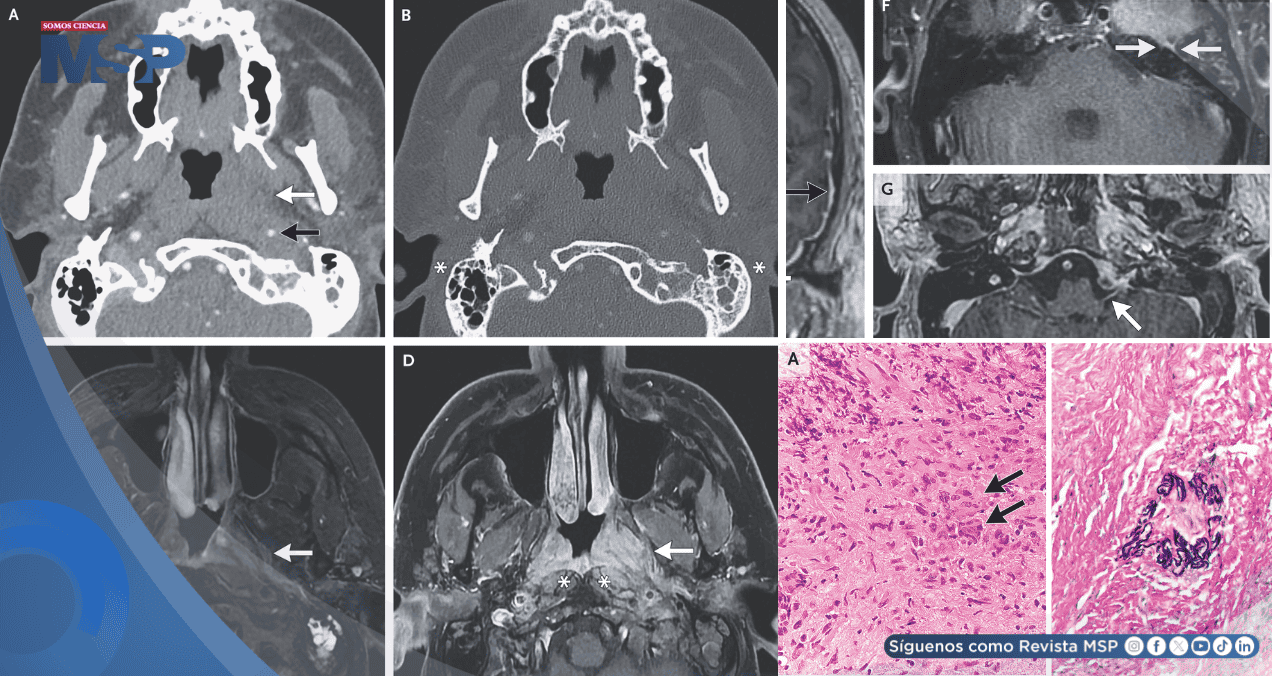

Las imágenes por resonancia magnética y tomografía computarizada mostraron una masa de tejido inflamado en la nasofaringe (la parte superior de la garganta, detrás de la nariz). Esta masa se extendía, afectando los músculos del cuello, la arteria carótida y, de manera crítica, múltiples nervios craneales, incluido el nervio facial.

El diagnóstico llegó con una biopsia de la masa nasofaríngea. El análisis histopatológico del tejido reveló la presencia de inflamación granulomatosa y vasculitis, que es una inflamación y daño directo a las paredes de los vasos sanguíneos.

Este hallazgo tisular se correlacionó con los análisis de sangre, que fueron positivos para un tipo específico de anticuerpo llamado PR3-ANCA. La combinación de estos hallazgos, la afectación de vías respiratorias superiores, la inflamación de vasos sanguíneos y los anticuerpos específicos, confirmó el diagnóstico de Granulomatosis con Poliangeítis (GPA).